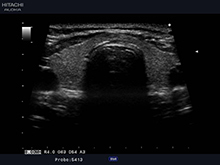

常盤台(ときわ台))近くの夜間救急対応の犬猫専門動物病院上板橋リズ犬猫病院の腹部超音波検査画像

当院では腹部超音波検査が実施可能です。レントゲン検査ではわからないリアルタイムの腸の動きや異物の有無、腫瘍、腹水の有無などを診断します。

レントゲン検査と腹部超音波検査を組み合わせて実施することにより診断することができる病気が多数あります。また腹部超音波検査を実施することにより病気の過少または過大評価を防ぐことにつながり、飼い主様にも納得していだける病気のご説明や治療が可能です。